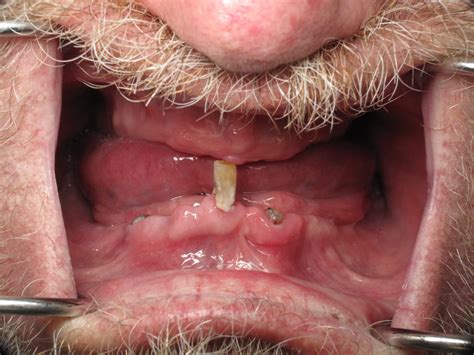

Broken Thigh Bone External Fixation. Fracture Of The Thigh Bone And ...